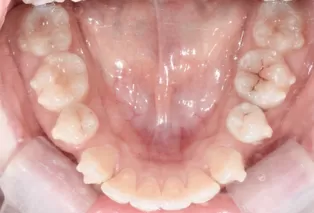

Photos intra-orales